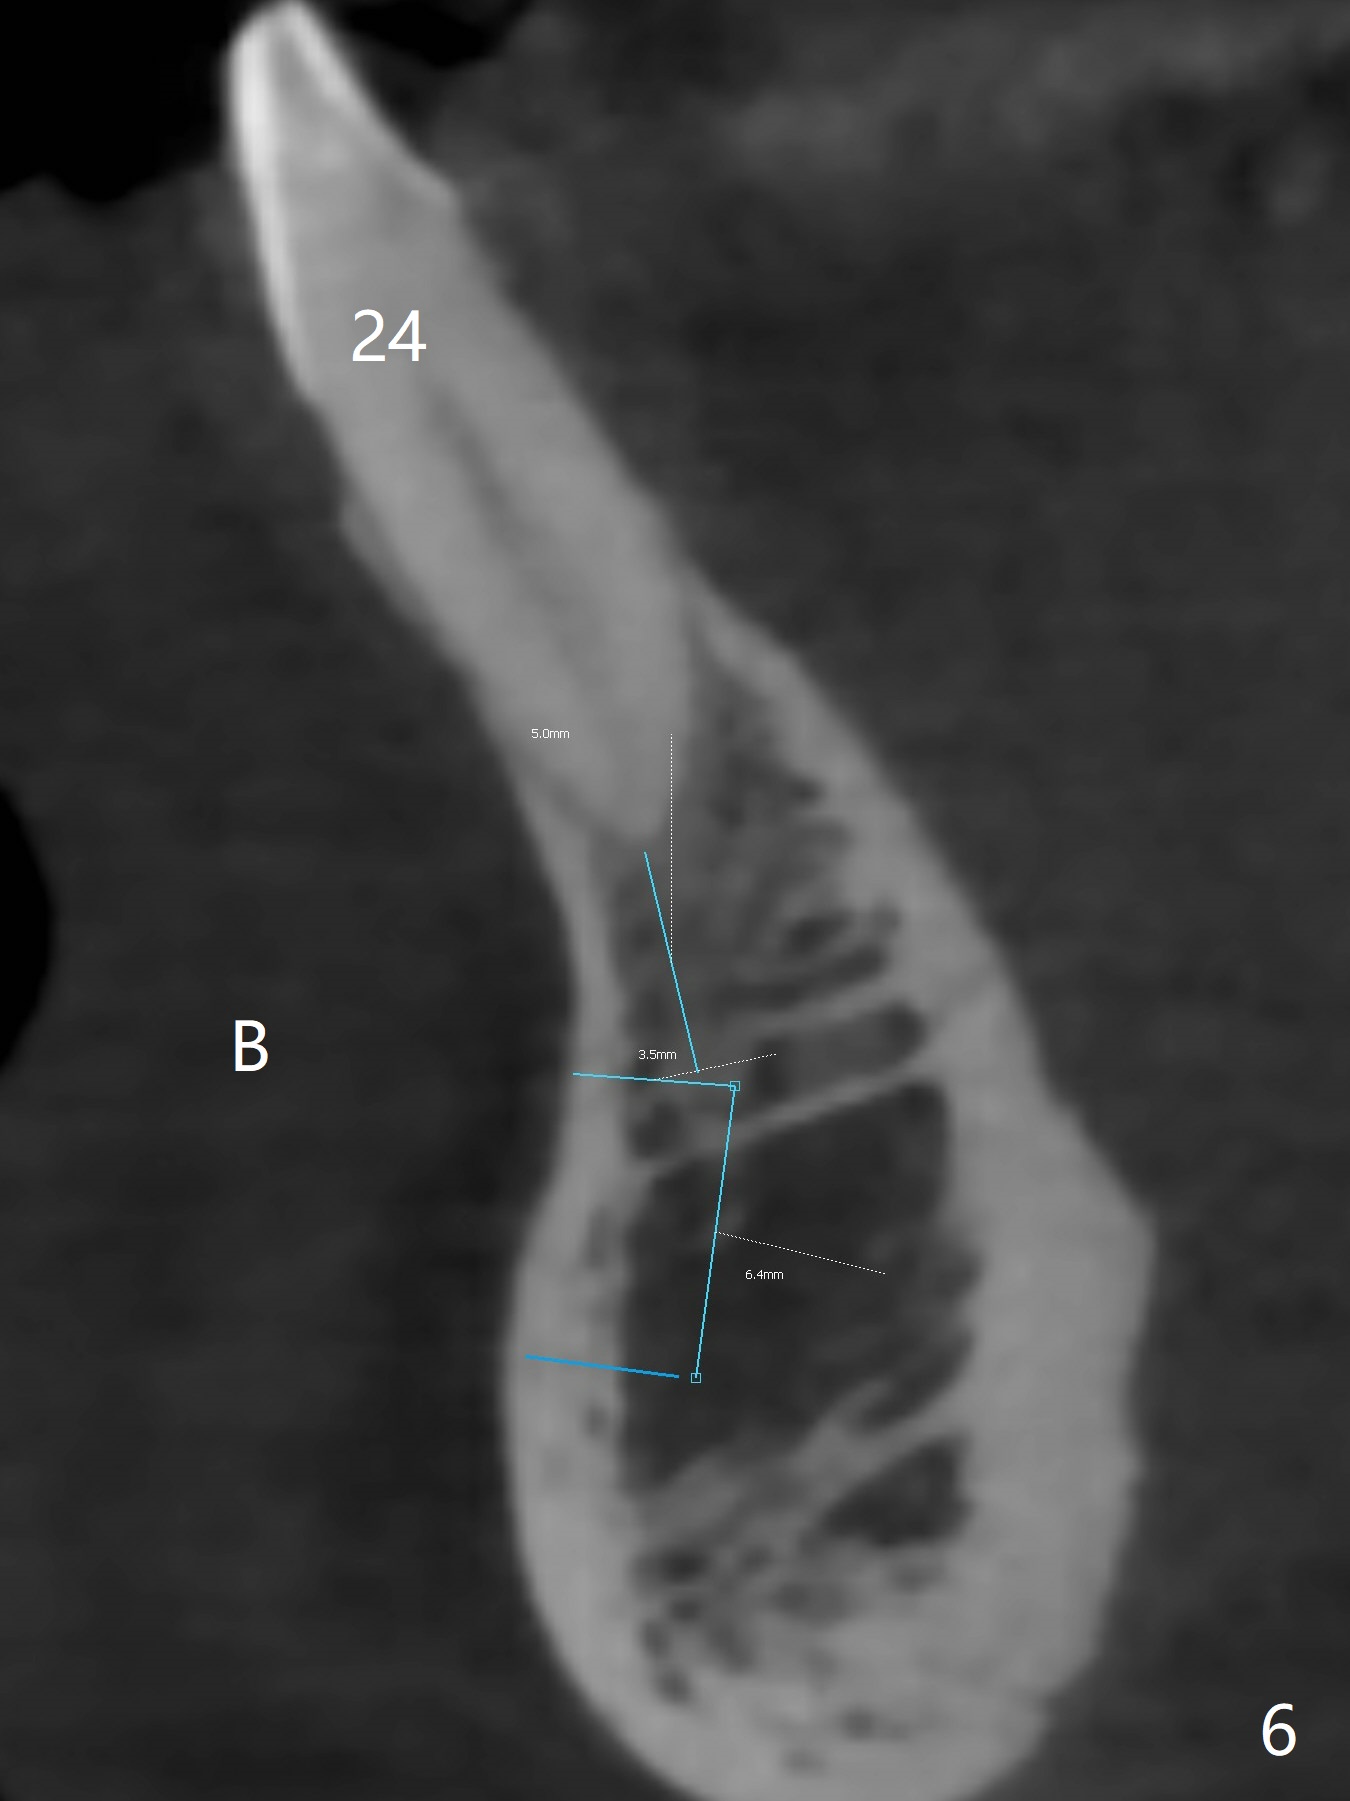

A 51-year-old woman lost the teeth #6 and 7 due to odontoma removal ~30 years ago. The area was restored with a FPD. The latter is removed with immediate implant at #8 8-9 months earlier. Particulate bone graft does not repair the bone deficiency at #6, 7 (Fig.2,3), although the soft tissue looks bulky (Fig.1). It appears that the palatal defect also needs a piece of bone block to fill in (Fig.4). The block will be harvested from the chin (Fig.5,6). If the block graft turns out to be impracticable, the periodontally compromised tooth #5 (bone loss, Fig.2,3,7) will be extracted for immediate implant. Initial osteotomy will be established in the palatal socket (Fig.8,9). Either a 2- (Fig.10) or 1- (Fig.11) piece implant will be placed. After wound healing, impression will be taken for a lab-fabricated provisional FPD.